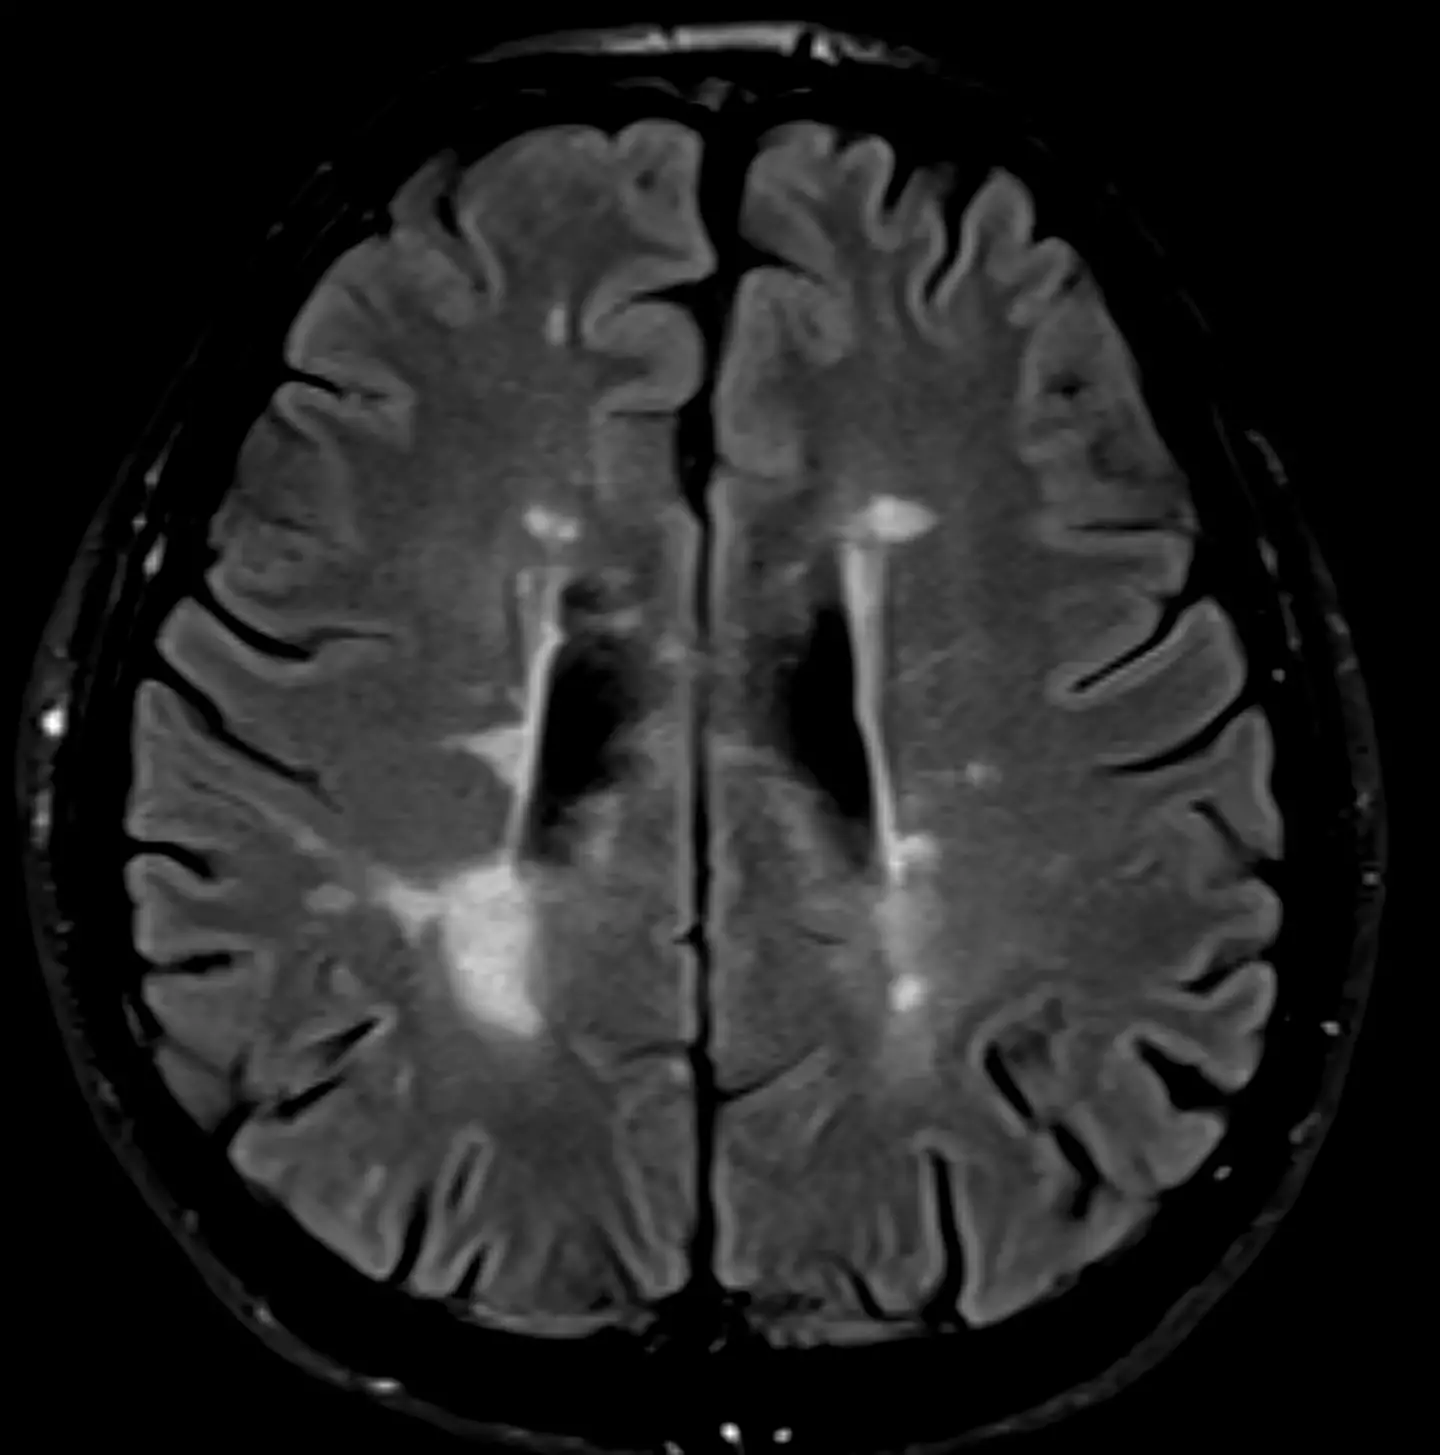

MS is a lifelong condition which affects both the brain and spinal cord, causing a wide range of varying symptoms including problems with vision, arm or leg movement, sensation or balance, muscle stiffness, numbness and problems with thinking, learning and planning.